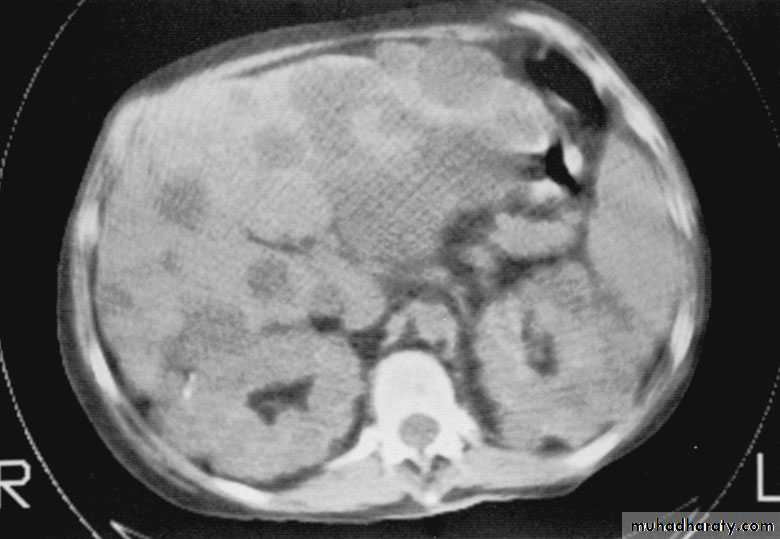

Congenital cystic kidney (polycystic kidney) (Adult cystic renal disease)

Autosomal dominant, transmitted by either parents, 50% of offspring's affected.

Both kidneys replaced by large number of cysts of variable size which make the kidney of large size.

The cysts contain clear fluid but sometimes blood.

The cysts progressively increase in size causing pressure atrophy of the renal parenchyma and pressing the ureter.

15% associated with cystic disease of liver, lung, pancreas or spleen.

U/S, IVU, CT scan, MRI